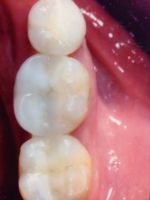

Before

After